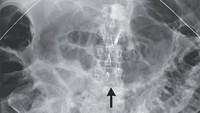

Setelah diperiksa pasien pertama terkontaminasi cacing gelang kecil yang disebut Strongyloides stercoralis pasca transplantasi ginjal. Ginjal tersebut berasal dari Karibia, sebelum pemilik organnya meninggal dunia. (Foto: New England Journal of Medicine)